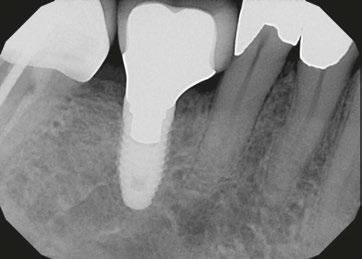

Figures 1A and 1B: 1A. Pre-extraction records. Patient presented with periodontal con cerns and extensive decay. 1B. Six LOCATOR® Implants (Zest Dental Solutions) were placed in strategic positions for a future fixed-prosthesis option

1A. 1B. 2.

Figures 1A–2: 1A. The DSST generate a gentle and progressive vertical and horizontal bone compaction that enhances initial implant stability regardless of the bone type or quality. This preserves the vascularity of the osteotomy while maintaining the peri-implant marginal bone and soft-tissue. 1B. The ULT implant RCN (A) preserves a ring of marginal bone reducing stress on the crestal cortical bone. This prevents undesired vascular compression while preserving the peri-implant soft tissue. The platform switching (B), has a smaller diameter implant-abutment connection. This leaves space for the biologic width that limits bone resorption while stabilizing the soft tissue that ensures excellent papillary esthetics. The micro-grooves (A) provide mechan ical stimulus that helps preserve marginal bone, increase the surface area of the implant and the ability of an implant to resist axial loads. 2. The ULT implant bone platform switching preserves a ring of marginal bone reducing stress on the crestal cortical bone. This prevents undesired vascular compres sion while preserving the peri-implant soft tissue

Figure 3: Preoperative panographic view of the maxillary and mandibular arches from the CBCT scan demonstrating anatomy that will impact implant placement Figure 4: Extraoral scan of the full maxillary and man dibular dentures that patient presented with, which she was unable to wear due to a significant gag reflex Figures 5A and 5B: Virtual planning of implant placement in the maxillary arch Figures 6A and 6B: Virtual planning of implant placement in the mandibular arch